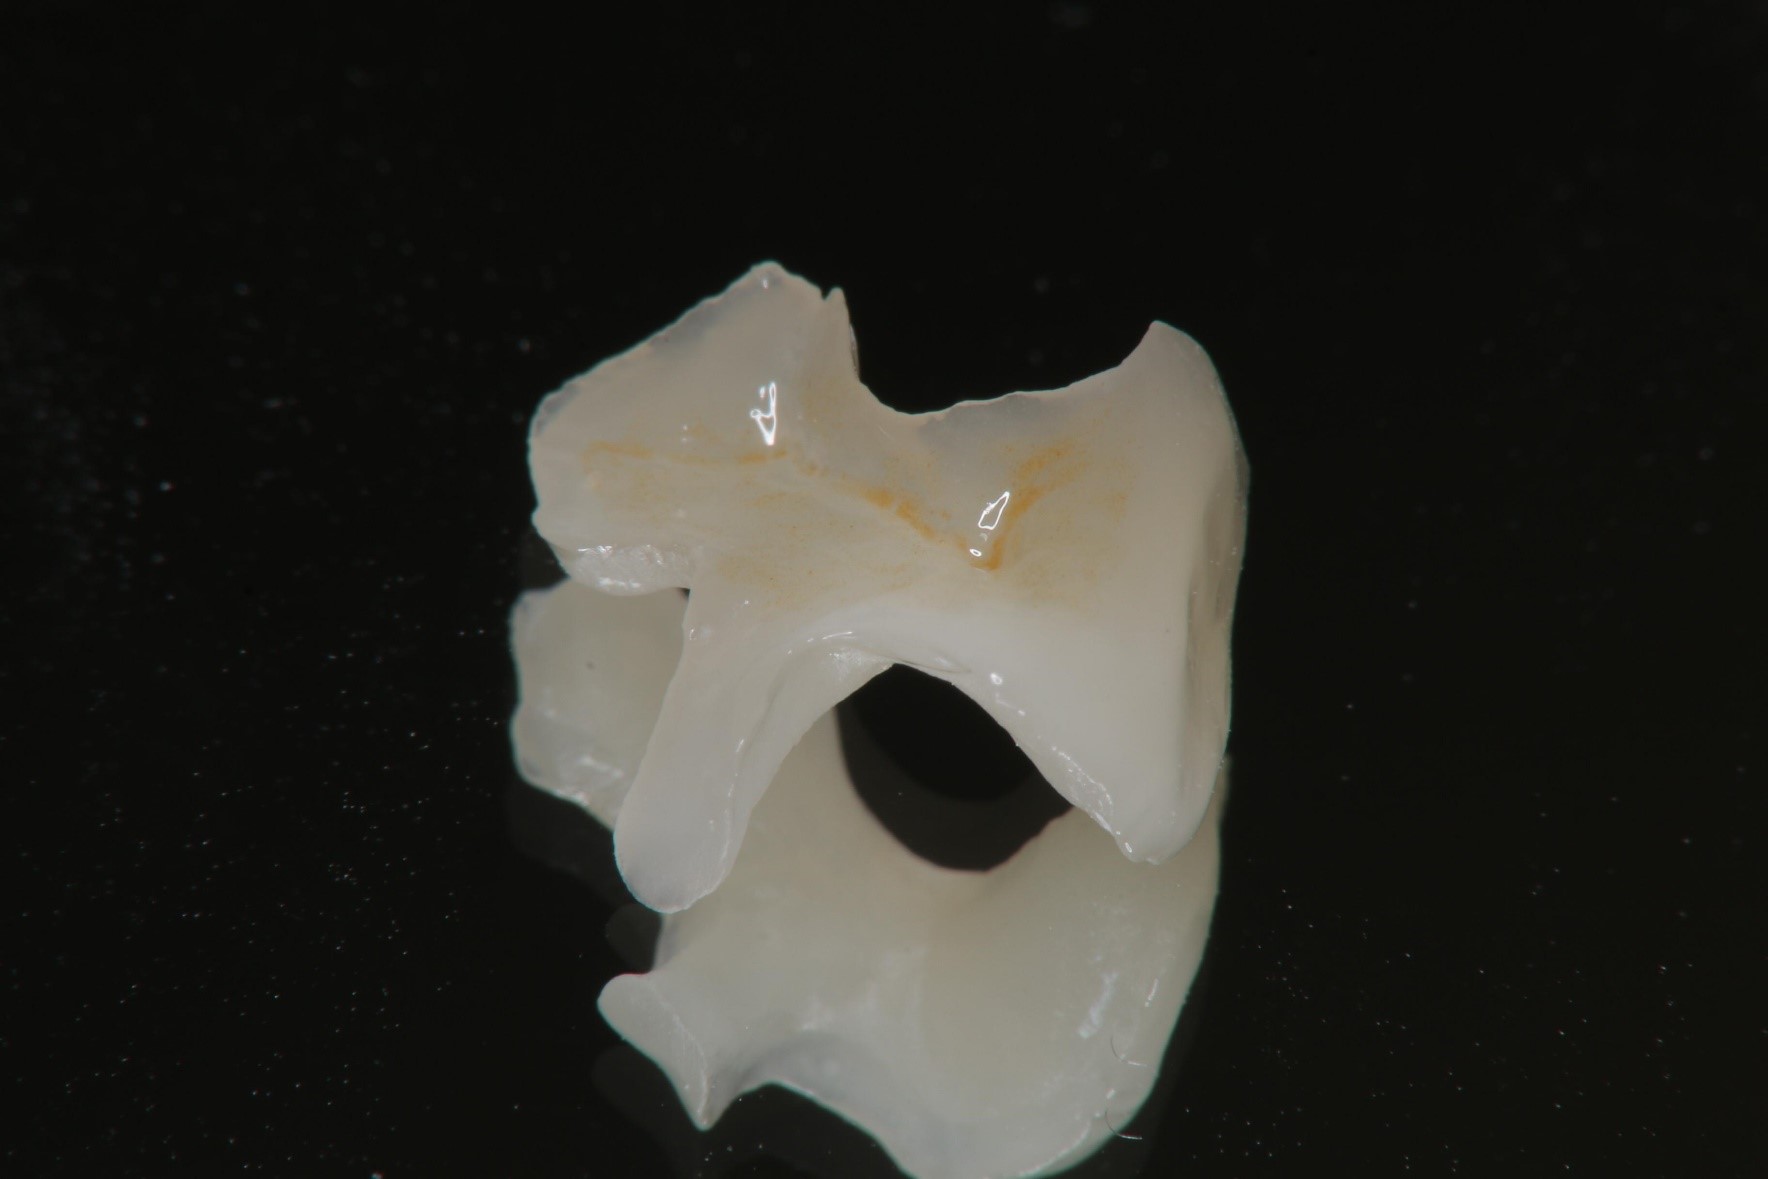

陶瓷崁體製作

陶瓷崁體